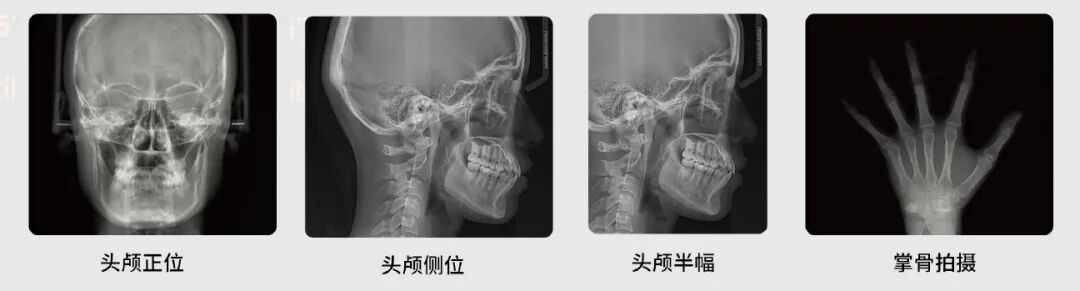

头颅摄影

全/半幅侧位、正位和掌骨拍摄模式可选

设备配备了高分辨率探测器,可根据医生需求拍摄正位、侧位片。为更好的优化辐射剂量,侧位片还可以选择全幅和半幅拍摄尺寸,为正畸提供精准清晰的数据影像。

该设备还具有掌骨摄影模式。医生可根据手掌指骨、腕骨及挠尺骨下端骨变化中心的发育程度确定骨龄。